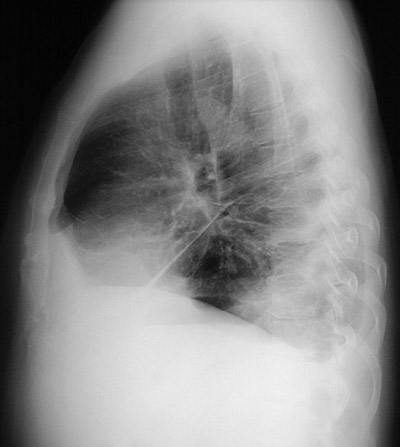

| The magnified view of the chest radiograph in lateral view above demonstrates fluid in the major fissure in a patient with left heart failure. The increased fluid in lymphatics around bronchi creates a circular outline to the bronchi as seen in cross section. The entire lateral view is seen below. |